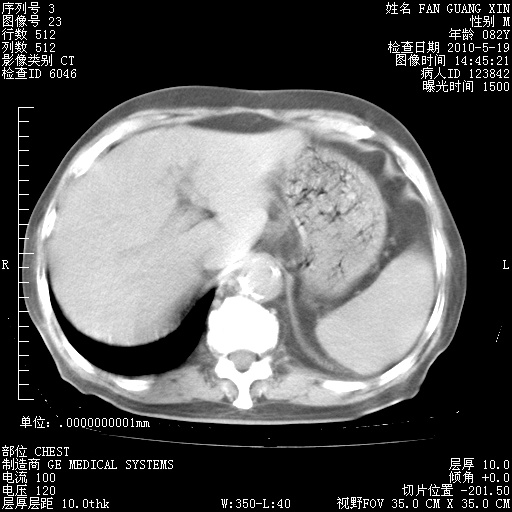

再治疗10天后的肺部CT

再治疗10天后的肺部CT 纵膈窗

从白细胞总数和中性比例看好像合并感染。肺部纹理好像比上次多,支气管炎?其他感染?

阅读此次胸部CT,肺间质渗出性改变较入院时有吸收。目前从体温、白细胞、中性分叶明显增高,肯定存在细菌感染(发生医院感染哦,若无消化道及泌尿系统等感染的依据,肺部感染可能大)。若你院头孢哌酮舒巴坦钠耐药率较高,同意你的方案,若48小时体温仍高,可考虑使用碳青霉稀类抗菌药物,同时可予超声雾化、注意滴数时加大液体量。白蛋白33.30g/L较低哦,需加强营养等支持治疗。